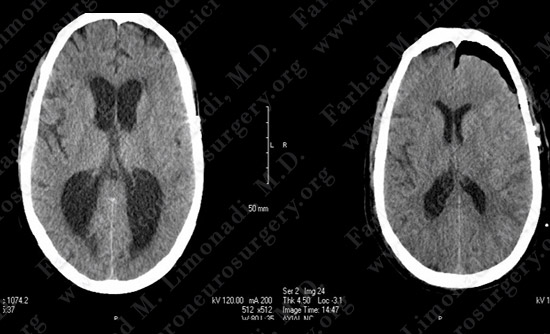

Current CT Post-op Day One

His CT scan demonstrated ventriculomegaly with evidence of obstructive hydrocephalus

MRI scan of the brain confirmed the CT finding and showed cerebral edema in left hemisphere due to tumor recurrence.